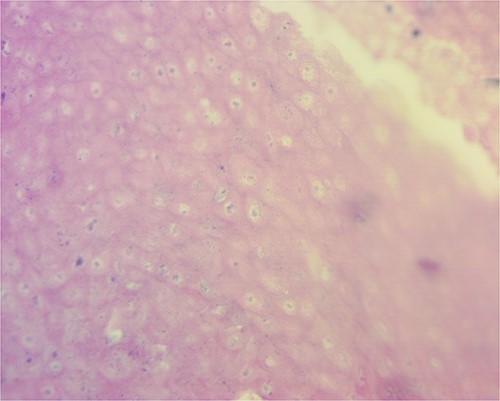

Macroscopically, the mass measured 20.1 * 13 * 5.8 cm. When incised, it showed a combination of yellowish areas with a friable calcified appearance and solid uncalcified whitish areas (Fig. 3). Histologically, sections were characterized by abundant ghost cells mixed with basophilic cells that imitate the cells of the basal layer of the hair follicle in the dermis (Fig. 4). There were extensive areas of calcification, necrosis and foreign body reaction, but no evidence of malignancy. These findings were most consistent with a giant pilomatrixoma.

Tumor microscopy revealing basophilic cells that mimic the stratus basalis interspersed with characteristic ghost cells.